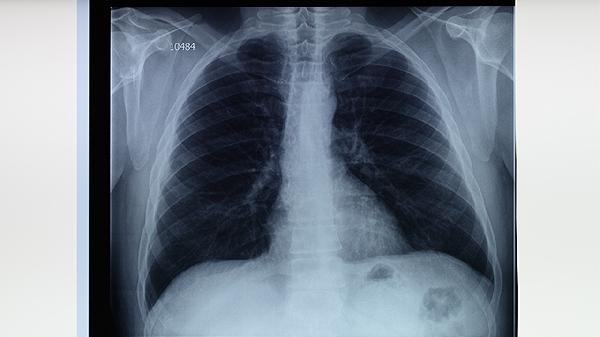

抗结核药物需坚持6-9个月规范治疗,不可自行增减药量。用药期间保持高蛋白饮食如鸡蛋、鱼肉,适量补充维生素B族和维生素C。每月复查肝肾功能、血常规及胸片,出现视力模糊、耳鸣等特殊症状需立即就诊。治疗全程避免与牛奶、酒精同服,不同药物需间隔2小时服用以保证疗效。